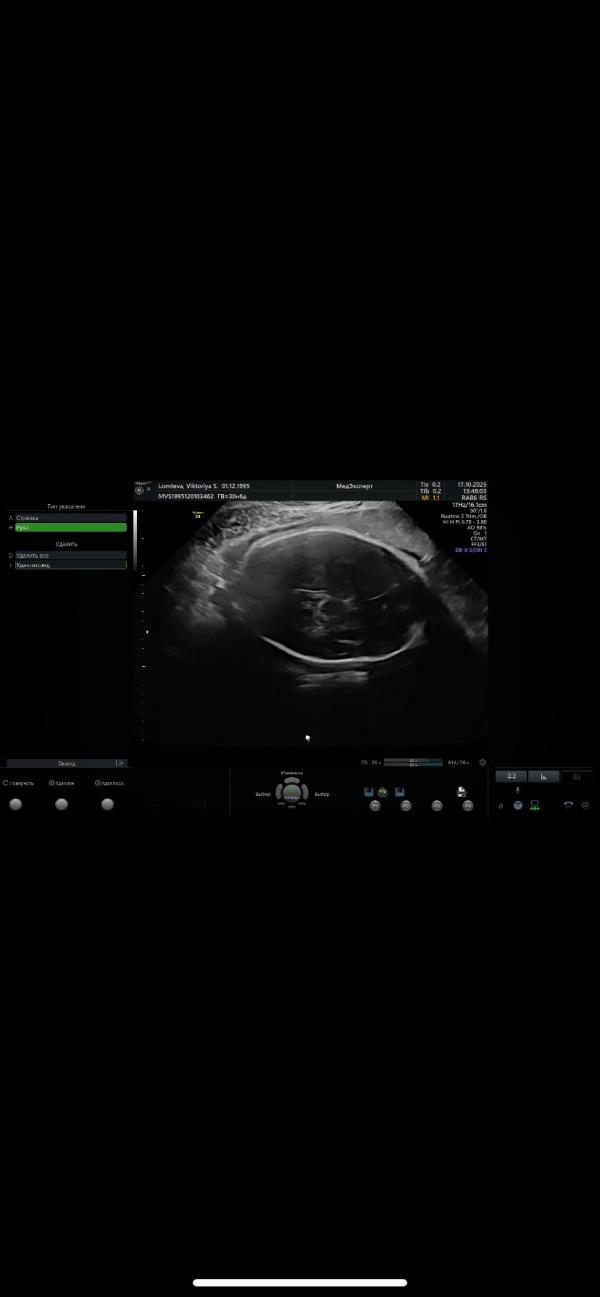

На третьем скрининге вытянутая форма черепа. У кого было такое? Потом все выровнялось?